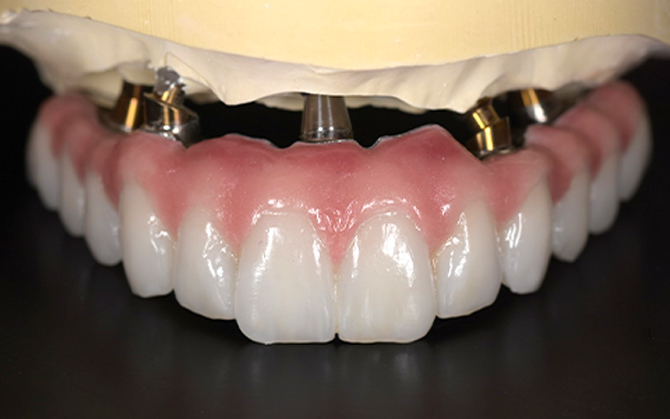

とびきり美しい上部構造

ただ治すのではなく、美しく治す。しかも、とびっきり美しく治すことにこだわっています。そのため、数々の賞を受賞する腕の良い歯科技工士と連携して歯をデザインしています。